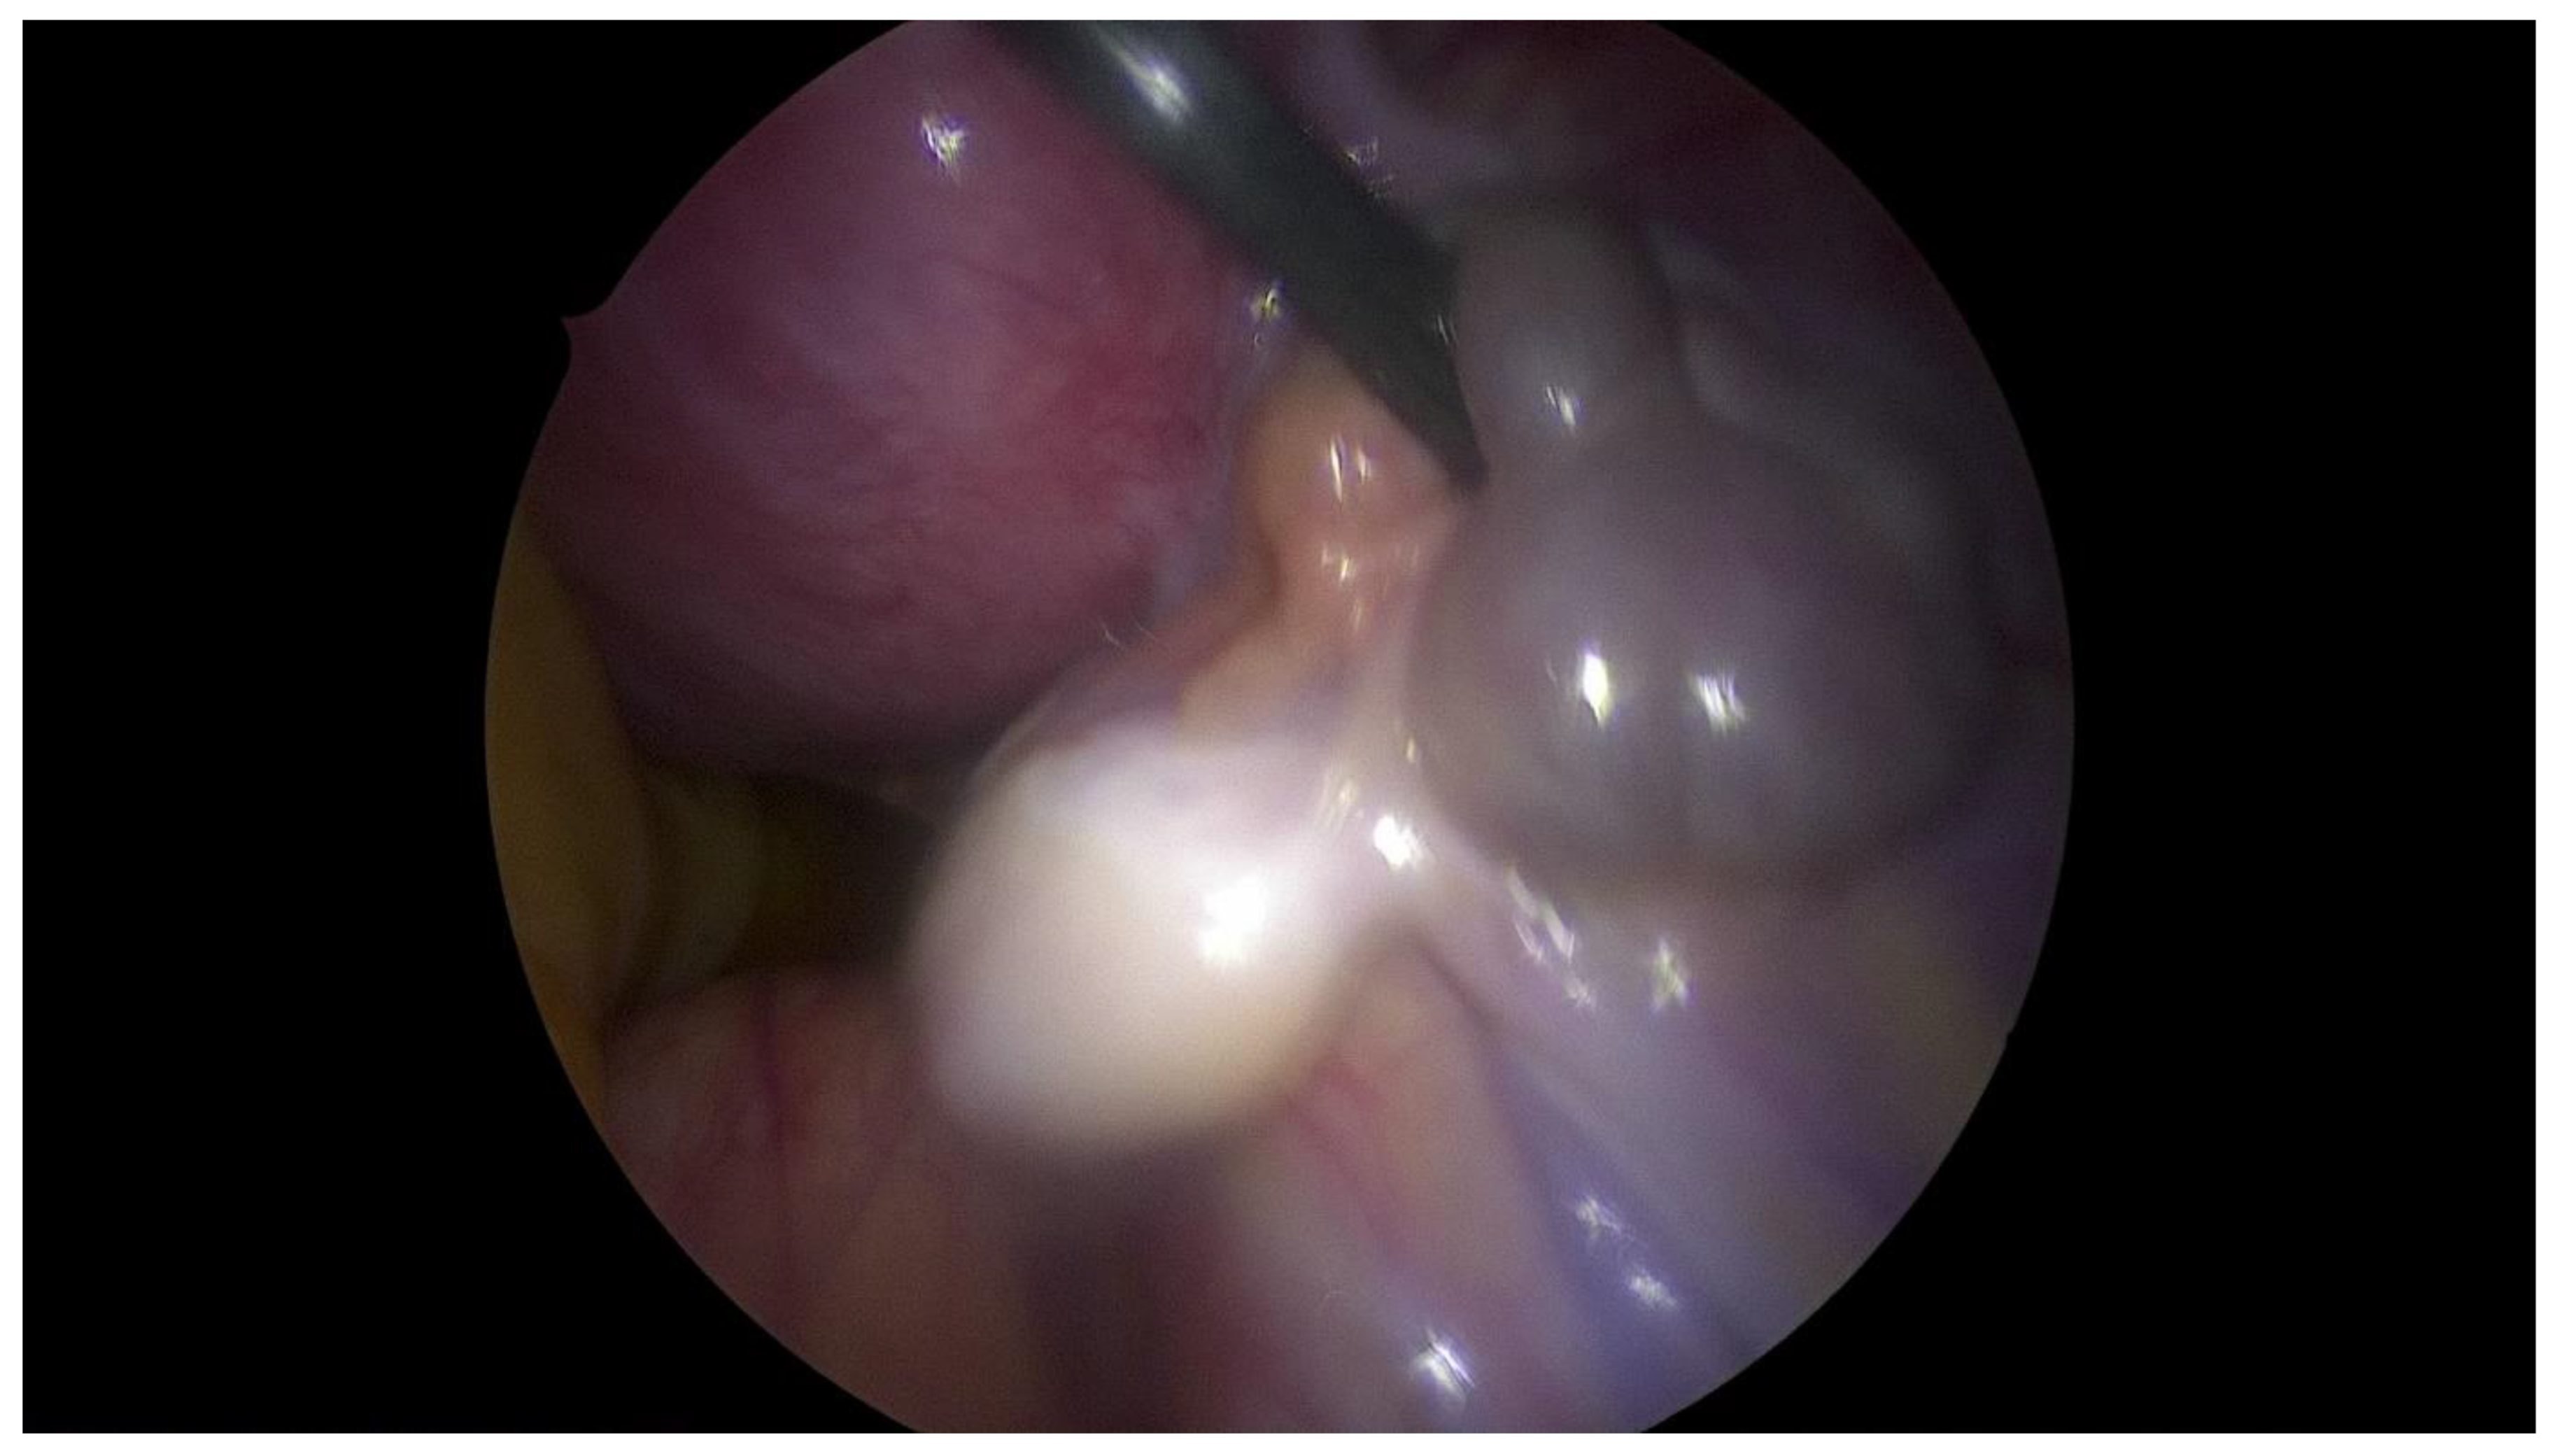

Step 3 Surgical management Surgery is necessary when acute abdominal symptoms are present. “Wait and see” approach is only possible when the clinical situation allows it. Perform laparoscopy and vaginoscopy in order to achieve the correct diagnosis and treat concomitant hematosalpinx and endometriosis [14]. Intraoperative US is helpful to evaluate the place of resection. Unnecessary lengthening the time to diagnosis, contributes to unindentent consequence. |